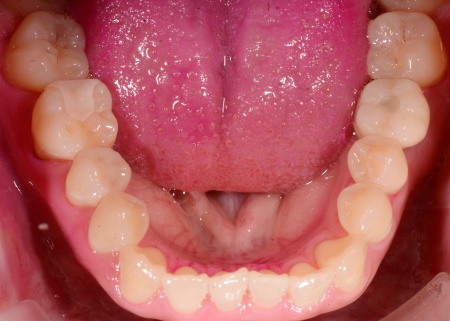

インプラントが顎の骨にしっかりと定着したことを確認したのち、インプラントの上に自然な見た目の人工歯を装着し、歯の形と噛み合わせを回復して治療を終了しました。